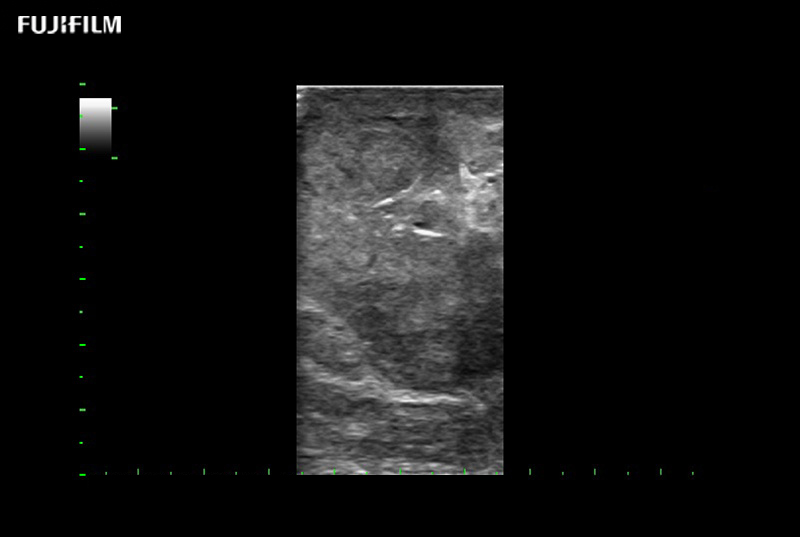

Curved array deep penetration “T” style finger-grip transducer for open surgical procedures.